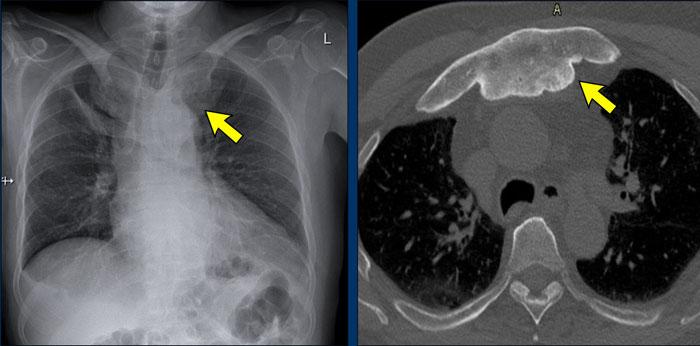

Sarcoidosis là một rối loạn đa hệ thống có căn nguyên chưa rõ, đặc trưng bởi sự hình thành các u hạt viêm không hoại tử bã đậu.

Biểu hiện cơ xương khớp của sarcoidosis xảy ra ở khoảng 20% bệnh nhân và bao gồm tổn thương khớp, tổn thương xương và bệnh lý cơ.

Tổn thương xương nguyên phát mà không có tổn thương các cơ quan khác là cực kỳ hiếm gặp. Thông thường, viêm khớp xuất hiện sớm trong diễn tiến của bệnh sarcoid; viêm khớp sarcoid mạn tính là hiếm gặp.

Biểu hiện cơ xương khớp thường gặp nhất của sarcoidosis là viêm khớp cấp tính, xảy ra như một phần của hội chứng Löfgren, đặc trưng bởi sự kết hợp của ban đỏ nút (erythema nodosum), hạch rốn phổi hai bên, viêm đa khớp và các triệu chứng toàn thân.

Dấu hiệu X-quang

- Khớp (Articular):

bào mòn khớp - Xương (Bone):

các tổn thương xương trong sarcoid có thể có dạng thấm lan (permeative) hay “ăn mòn như mối đục” (moth-eaten), tiêu xương hoặc xơ cứng. Các tổn thương này rất đặc trưng. - Sụn (Cartilage):

hẹp khe khớp là biểu hiện không thường gặp. - Phân bố (Distribution):

Điển hình là tổn thương nhiều khớp với phân bố đối xứng, xem minh họa. - Dấu hiệu bổ sung (Extra findings): Có nhiều biểu hiện đa dạng và do đó cũng có nhiều biểu hiện lâm sàng và X-quang khác nhau.

- Phần mềm (Soft tissue): viêm ngón tay (dactylitis), bệnh lý cơ (myopathy).

U hạt dạng ren (Lace-like granulomas)

Nhiều tổn thương xương trên một bệnh nhân sarcoid.

Các tổn thương tiêu xương khá điển hình và được mô tả có dạng ren hoặc dạng bè xương.

Một khi đã nhận ra hình ảnh này, bạn sẽ dễ dàng nhận diện nó trong các trường hợp khác.

Hình ảnh cho thấy một tổn thương tiêu xương ở đầu xa xương quay (mũi tên xanh) với phá hủy xương bè và vỏ xương trên một bệnh nhân sarcoid.

Có phá hủy xương ở cả hai phía của khớp liên đốt ngón tay cái kèm theo lan rộng ra ngoài xương của mô u hạt (mũi tên đen).